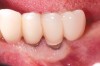

Dental implants have revolutionized the way in which clinicians treat and restore partially and fully edentulous patients and have demonstrated success for managing a broad range of clinical dilemmas. While implants have been highly predictable and have achieved long-term success, they are not immune from complications associated with improper treatment planning, poor surgical and prosthetic execution, material failure, and inadequate or infrequent maintenance. Among these problems are the biologic complications of peri-implant mucositis and peri-implantitis, which are inflammatory conditions in the soft and/or hard tissues surrounding dental implants (Figure 1 through Figure 4).1,2

Fig 2. Radiograph suggested moderate bone loss around the implants.

Figure 2